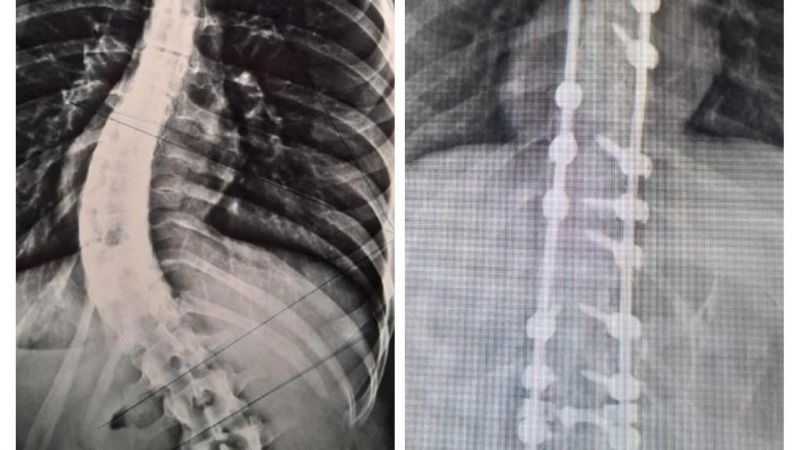

En el Hospital Interzonal San Juan Bautista, de manera exitosa, se realizó días atrás una nueva cirugía para corrección de columna vertebral en una joven paciente que presentaba escoliosis dorsolumbar grave

En la Cirugía, que tuvo una duración de más de 4 horas de quirófano, se logró la reducción de la deformación dorsolumbar mediante la colocación de barras y tornillos pediculares. Los Traumatólogos que estuvieron a cargo fueron Nicolás Flores Kanter y Pablo Ovejero -este último en colaboración por parte del Hospital de Niños-; con la anestesista, Dra. Adriana Bustos, y los instrumentadores Aldo Espilocin y Claudia Sánchez.